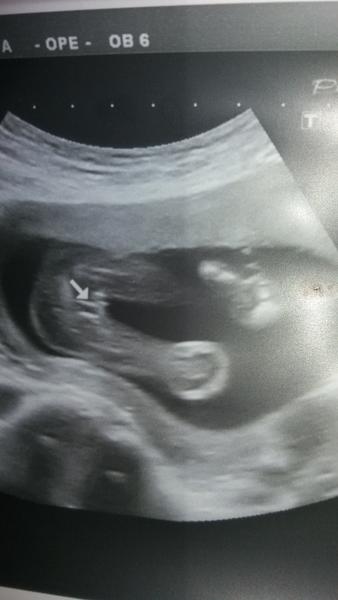

@luccyj ma nozky hodne u sebe,tak to fakt muze byt i kluk s tohle pytlik. Skoda,ze miminko nemelo nohy od sebe. A tip od doktora?

Take jsem celou dobu byla presvedcena o holcicce.No uvidime.Snad se pristi mesic nebude tak stydet a nozky roztahne 🙂